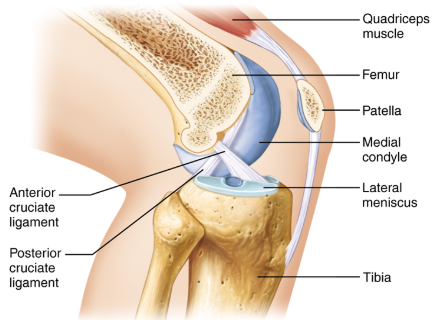

What is the tibiofemoral joint?

The knee joint.

What is the joint shown here?

The tibiofemoral joint.

What is the joint shown here?

The tibiofemoral joint.

What ligament is shown here?

Patellar ligament.

What ligament is shown here?

Anterior cruciate ligament.

What ligament is shown here?

Anterior cruciate ligament.

What does the anterior cruciate ligament prevent?

The anterior cruciate helps prevent anterior sliding of the tibia.

What ligament is shown here?

Posterior cruciate ligament.

What ligament is shown here?

Posterior cruciate ligament.

What does the posterior cruciate ligament prevent?

The posterior cruciate prevents forward sliding of the femur or backward displacement of the tibia.

What is the highlighted fibrocartilage?

Lateral meniscus.

What is the highlighted fibrocartilage?

Lateral meniscus.

What is the highlighted fibrocartilage?

Medial meniscus.

What is the highlighted fibrocartilage?

Medial meniscus.